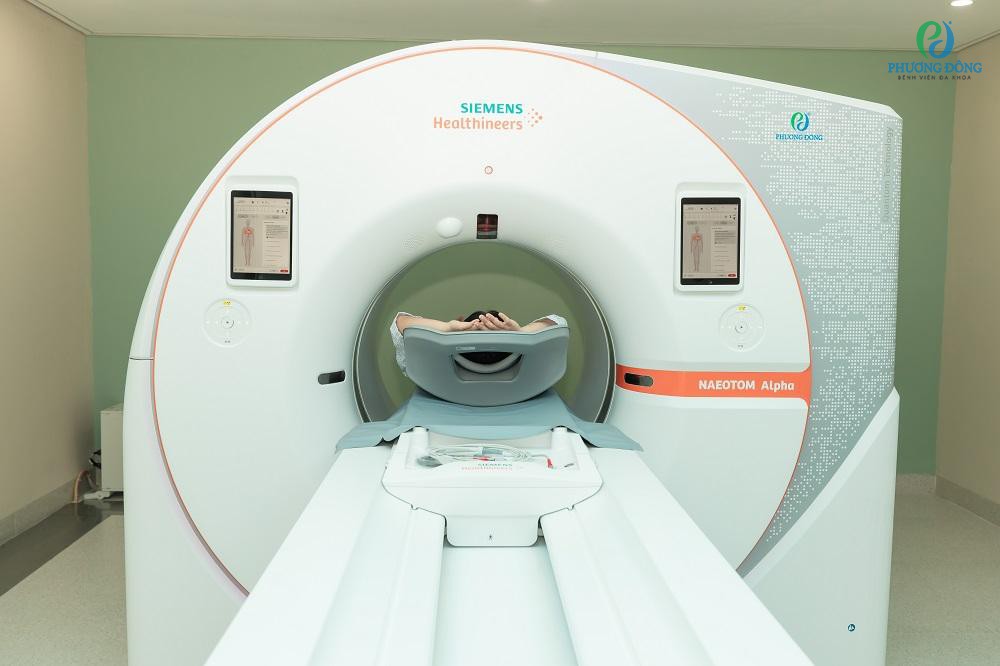

[Theo Cafef.vn] Hệ thống cắt lớp lượng tử Naeotom Alpha đang xếp hạng nhất thế giới về tốc độ chụp toàn thân (chưa tới 1 giây) đã chính thức được vận hành tại BV Phương Đông. Đây thực sự là bước đột phá mới trong chẩn đoán sớm đột quỵ, tim mạch, ung thư - nhóm nguyên nhân hàng đầu gây tử vong hiện nay.

Công nghệ của tương lai, vượt qua mọi giới hạn trong chẩn đoán hình ảnh y khoa

Tính đến nay, khi việc nghiên cứu phát triển công nghệ CT đếm photon đã trải qua hơn 2 thập kỷ thì Naeotom Alpha vẫn giữ nguyên vị trí là hệ thống chụp cắt lớp lượng tử toàn thân duy nhất được Cục Quản lý thực phẩm và Dược phẩm Hoa Kỳ (FDA) công nhận lâm sàng.

Hệ thống Naeotom Alpha vượt qua mọi giới hạn về lát cắt trong chụp CT, cho hình ảnh sắc nét nhất thế giới, lên đến 110µ, đặc biệt hữu ích trong tầm soát sớm đột quỵ, tim mạch, ung bướu cũng như nhiều mầm mống bệnh lý trong cơ thể.

Với lát cắt mỏng nhất thế giới, chỉ 0.2mm, Naeotom Alpha trả kết quả đánh giá mạch vành ở mọi điểm vôi hóa (trên 1000 điểm), chẩn đoán kích thước mạch vành tương đồng nhất với hình chụp mạch can thiệp. Độ chính xác rất cao nên có thể giảm thiểu việc thực hiện thêm các thủ thuật xâm lấn như chụp động mạch vành để chẩn đoán ở các bệnh nhân nguy cơ cao. Đặc biệt, công nghệ đếm photon đã nâng tầm việc đánh giá, quản lý bệnh nhân tim mạch, nhất là bệnh động mạch vành (đã đặt stent, có kim loại trong người, đeo máy tạo nhịp tim…) hiện nay chưa có hệ thống CT nào làm được vì bị nhoè ảnh do nhiễm kim loại.

Nói về tốc độ chụp toàn thân nhanh nhất thế giới, chưa tới 1 giây, chính là thế mạnh vượt trội giúp khắc phục hạn chế của CT truyền thống, tránh nhiễu do chuyển động hay có kim loại khi chụp. Ảnh chụp sắc nét cho phép tinh chỉnh đến từng điểm nhỏ trong não, nhờ thế, bác sĩ dễ dàng nhận dạng chính xác tổn thương mô trắng/mô xám rất sớm, thấy rõ khối nhồi máu kích thước siêu nhỏ - mối nguy cơ hàng đầu gây đột quỵ; đồng thời, chớp "cửa sổ vàng" trong điều trị.

Cũng với những tính năng ưu việt đó, hệ thống Naeotom Alpha có thể nhìn thấy rõ từng bất thường siêu nhỏ như nốt mờ dưới 3mm ở phổi, tổn thương biểu mô gan dưới 1cm hay phát hiện vi vôi hoá,... - vốn rất khó quan sát bằng CT truyền thống. Từ đó, bác sĩ dễ dàng phát hiện mầm mống giai đoạn sớm của các loại ung thư phổ biến như ung thư phổi, ung thư gan, ung thư vú, ung thư não,...

An toàn hơn cho sức khỏe và có thể ứng dụng trong khám sức khỏe định kỳ

Một đột phá góp phần định vị công nghệ này ở nhóm dẫn đầu thế giới đó chính là tích hợp toàn diện trí tuệ nhân tạo (AI) có thể phát hiện chính xác tổn thương siêu nhỏ rất nhanh, từ đó, nâng cao giá trị chẩn đoán và độ an toàn cho bệnh nhân.

Trí tuệ nhân tạo chuyên sâu trong hệ thống Naeotom Alpha không chỉ cho phép chụp CT nhanh bứt phá, hình ảnh sắc nét nhất, mà đặc biệt hơn, giảm thiểu liều tia X sử dụng, với lượng bức xạ chỉ tương đương như môi trường tự nhiên (giảm tới khoảng 90% so với CT dòng thấp). Nỗi lo về phơi nhiễm bức xạ gần như được xóa bỏ. Lượng thuốc cản quang dùng cũng giảm tới 68%, giúp hạn chế nguy cơ suy thận hay các tác dụng phụ khác.

Theo đó, việc tầm soát sức khỏe định kỳ với các danh mục khám có chụp CT công nghệ đếm photon, trở nên dễ dàng hơn bao giờ hết. Bạn hoàn toàn có thể nắm bắt những lợi ích vàng trong tầm soát chủ động của Naeotom Alpha mà không phải lo lắng về các rủi ro cho sức khỏe. Cụ thể như: thực hiện chụp CT tại các vùng muốn tầm soát như hàm - mặt, sọ não - mạch máu, lồng ngực - phổi, ổ bụng, toàn thân,... Đây thực sự là bước tiến quan trọng trong nâng cao hiệu quả chẩn đoán sớm và điều trị các bệnh lý nguy hiểm, mang lại hy vọng sống khỏe mạnh cho hàng triệu người.

Được biết, hệ thống cắt lớp lượng tử NAEOTOM Alpha sẽ chính thức ra mắt tại BV Phương Đông vào ngày 7/8 tới đây. Điều này mở ra cơ hội cho người dân Việt Nam, đặc biệt ở miền Bắc, tiếp cận các công nghệ tầm soát sức khoẻ hiện đại nhất thế giới ngay trong nước, tiết kiệm chi phí hơn hẳn so với việc phải ra nước ngoài như trước kia.